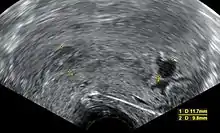

Ultrasound criteria

A review article in The New England Journal of Medicine based on a consensus meeting of the Society of Radiologists in Ultrasound in America (SRU) has suggested that miscarriage should be diagnosed only if any of the following criteria are met upon ultrasonography visualization:[95]

| Crown-rump length of at least 7 mm and no heartbeat. | Crown–rump length of less than 7 mm and no heartbeat. | [95][96] |

| Mean gestational sac diameter of at least 25 mm and no embryo. | Mean gestational sac diameter of 16–24 mm and no embryo. | [95][96] |

| Absence of embryo with heartbeat at least 2 weeks after an ultrasound scan that showed a gestational sac without a yolk sac. | Absence of embryo with heartbeat 7–13 days after an ultrasound scan that showed a gestational sac without a yolk sac. | [95][96] |

| Absence of embryo with heartbeat at least 11 days after an ultrasound scan that showed a gestational sac with a yolk sac. | Absence of embryo with heartbeat 7–10 days after a scan that showed a gestational sac with a yolk sac. | [95][96] |

| Absence of embryo at least 6 weeks after last menstrual period. | [95][96] | |

| Amniotic sac seen adjacent to yolk sac, and with no visible embryo. | [95][96] | |

| Yolk sac of more than 7 mm. | [95][96] | |

| Small gestational sac compared to embryo size (less than 5 mm difference between mean sac diameter and crown-rump length). | [95][96] |